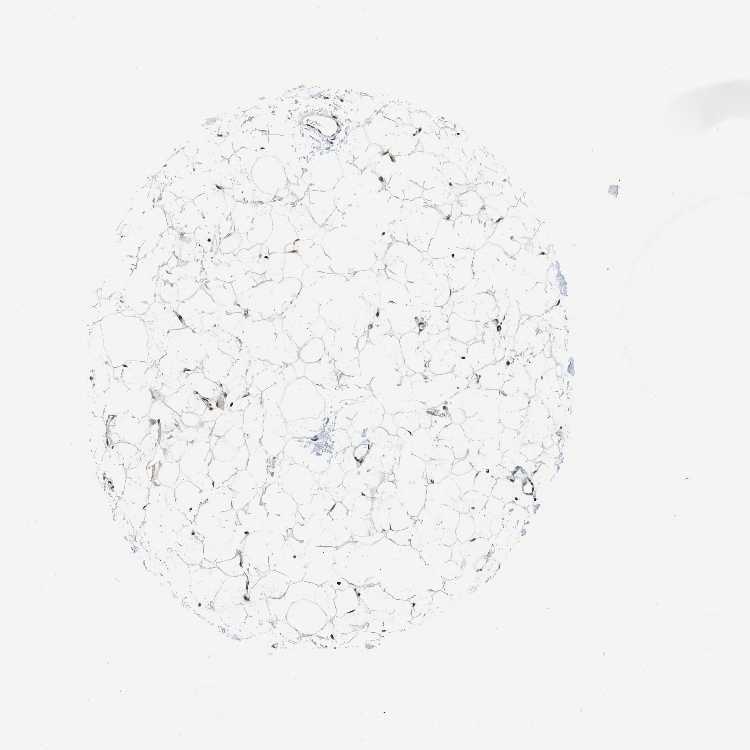

ADIPOSE TISSUE - Antibody stainingi

Antibody staining in the annotated cell types in the current human tissue is reported as not detected, low, medium, or high, based on conventional immunohistochemistry profiling in selected tissues. This score is based on the combination of the staining intensity and fraction of stained cells.

Each image is clickable and will lead to virtual microscopy that enables deeper exploration of all samples and also displays staining intensity scores, fraction scores and subcellular localization as well as patient and tissue information for each sample.

Antibody CAB017544

Adipocytes High